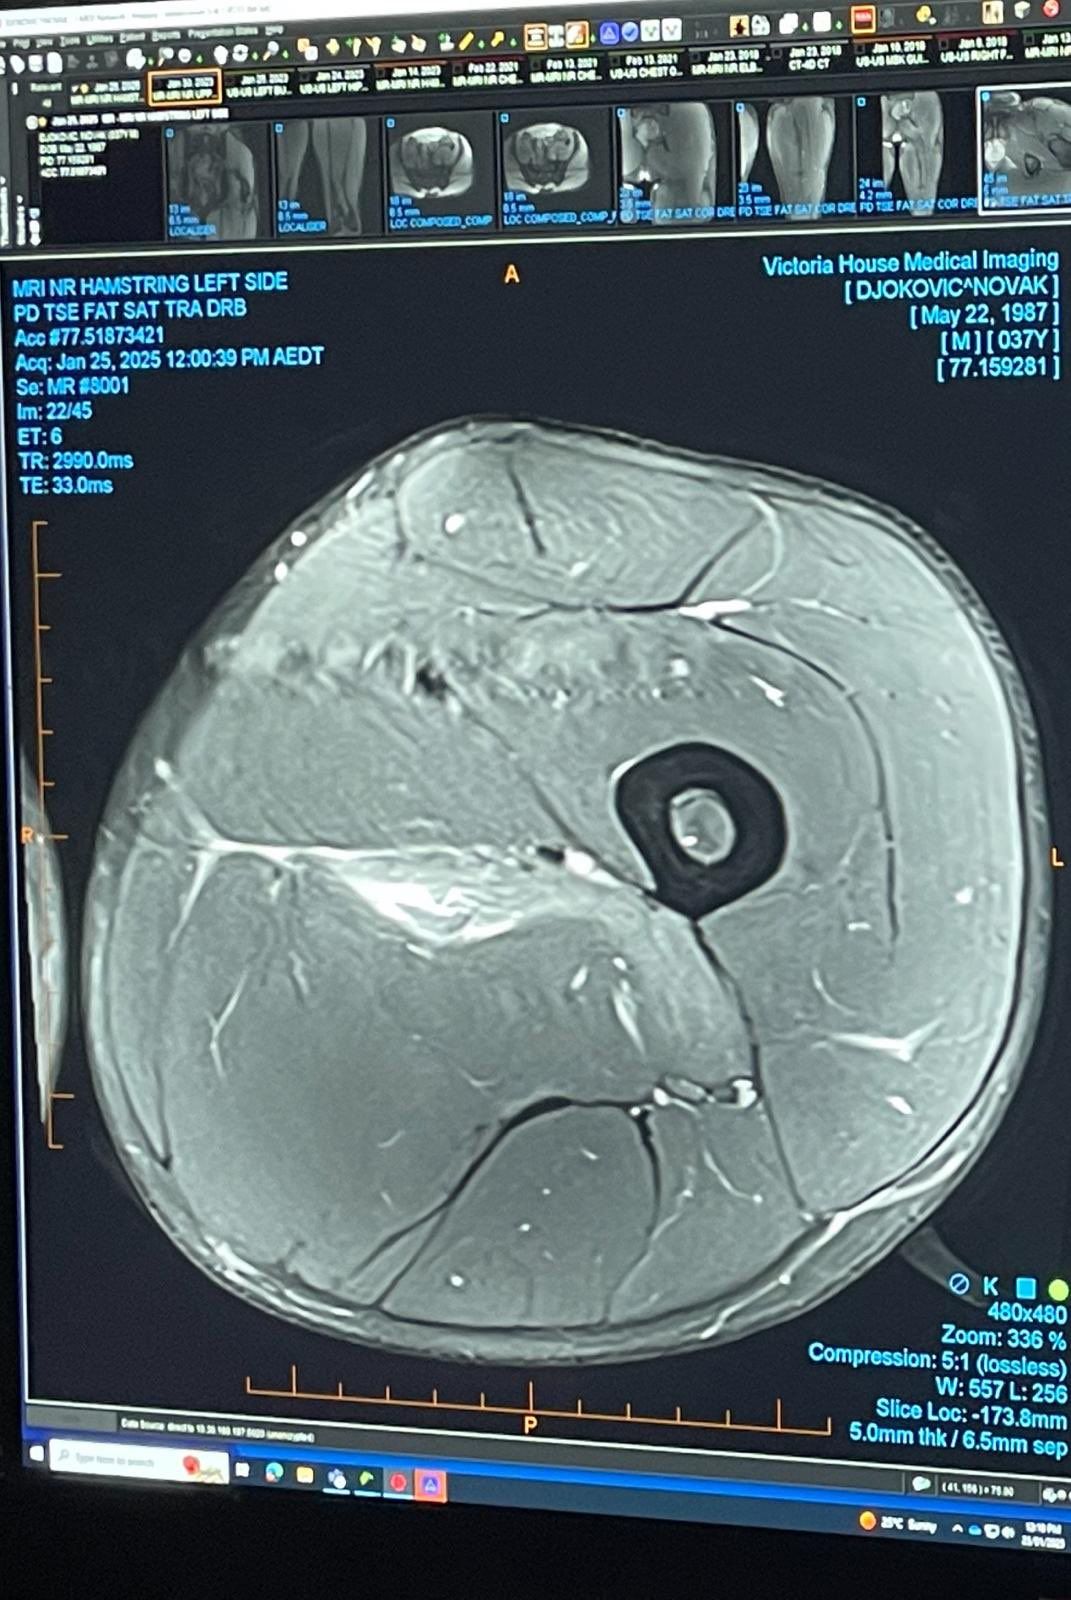

Джокович выложил фото МРТ бедра: для «экспертов» по травмам

Седьмая ракетка мира серб Новак Джокович опубликовал в своих социальных сетях фотографию с МРТ левого бедра.

«Подумал, что оставлю это здесь для всех «экспертов» по спортивным травмам», — подписал фото Джокович.